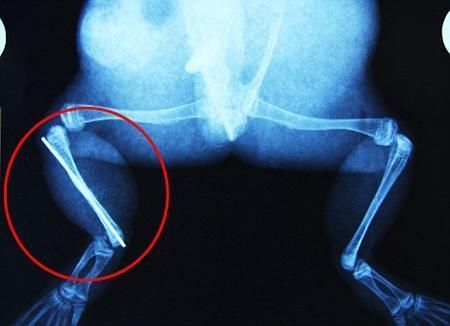

環(huán)球網(wǎng)4月2日報(bào)道 據(jù)《每日郵報(bào)》報(bào)道,上個(gè)月,南非大牛蛙布魯萊的右小腿被鄰居家的一只狗咬到,導(dǎo)致粉碎性骨折,現(xiàn)在經(jīng)過2個(gè)小時(shí)的手術(shù),它的斷腿已經(jīng)被接上,它也因此成為有史以來第一只通過外科手術(shù)用鋼針接上斷腿的青蛙。

布魯萊的主人,居住在南非約翰內(nèi)斯堡附近的62歲的安妮·米恩斯說:“我對這只青蛙如此關(guān)心,人們一定認(rèn)為我瘋了,但是我無法眼睜睜看著它那么痛苦。青蛙因其靈活的腿腳而著稱,一想到布魯萊的腿里要留下一個(gè)薄金屬片,我就感到心痛。然而我知道,如果不進(jìn)行手術(shù),布魯萊以后就沒辦法動(dòng)彈了。因此我匆匆趕到獸醫(yī)那里,央求他給這只可憐的青蛙動(dòng)手術(shù)。這位獸醫(yī)整天救助小貓小狗,他很難理解為什么我這么擔(dān)心一只青蛙,但是最終他還是答應(yīng)了給布魯萊做手術(shù)。手術(shù)后是幾個(gè)小時(shí)的焦急等待,我們希望它能快快蘇醒過來。不過現(xiàn)在它的傷口已經(jīng)愈合,又能在花園里跳來跳去了。X光照射顯示,它會(huì)恢復(fù)的跟以前一樣。”

野生生物專家安妮經(jīng)常為學(xué)校寫教材,她認(rèn)為這是人類第一次通過手術(shù)給一只青蛙接斷腿。在手術(shù)開始階段,獸醫(yī)把少量給狗用的麻醉藥注入到這只青蛙體內(nèi),讓它失去知覺。然后他在布魯萊的斷腿上切開一個(gè)小口,把一根小鋼針植入腿里。最后獸醫(yī)給它縫了9針,把切口縫合在一起。僅僅幾周后,布魯萊就能在安妮家附近活動(dòng)了。這只青蛙大約已有25歲,主要以嚙齒動(dòng)物、蛇和其他青蛙為食。布魯萊所屬的牛蛙種群正在不斷減小,目前只能在非洲南部的濕地里才能看到這種青蛙。

安妮有2個(gè)孩子,她已經(jīng)從事20多年兩棲動(dòng)物保護(hù)工作。她認(rèn)為鄰居家的狗狗在把布魯萊從地下刨出來的時(shí)候,它正在地下冬眠、她說:“世界上只有這個(gè)地區(qū)能看到這種牛蛙,這種青蛙現(xiàn)在變得越來越稀少。因?yàn)槲覐氖乱吧锉Wo(hù)工作,因此認(rèn)識很多兩棲動(dòng)物專家,但是以前他們誰也沒見過這種事情?吹讲剪斎R越來越健康我非常開心,F(xiàn)在還需要一段時(shí)間,它的金屬腿和它的骨骼才能融為一體,那時(shí)布魯萊會(huì)跟以前一樣健康。我們認(rèn)為這個(gè)過程需要幾周時(shí)間,但是一旦它完全康復(fù),我希望把它放歸大自然,讓它重新回到它最鐘愛的濕地里!